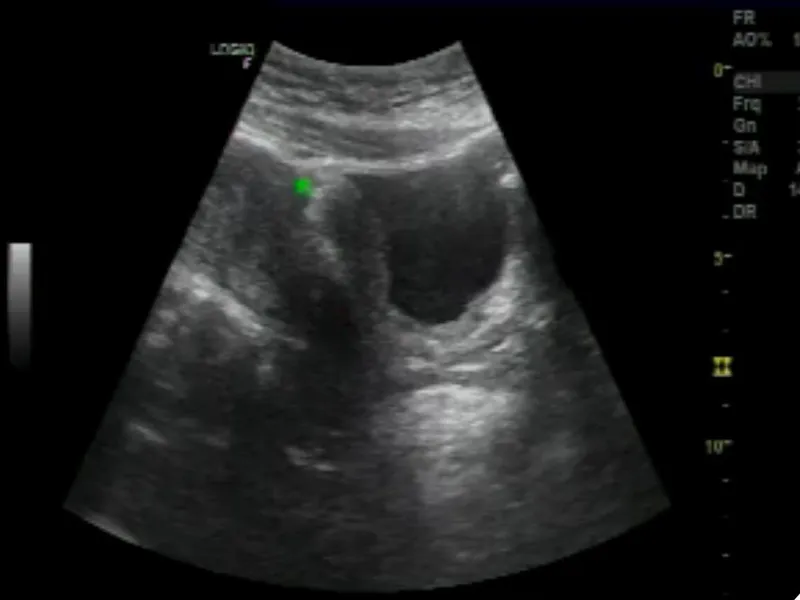

Hiện nay, bệnh sỏi thận rất phổ biến ở các nước nhiệt đới nóng ẩm như Việt Nam, thường hình thành khi nước tiểu bị lắng cặn, khiến các khoáng chất kết dính lại với nhau.